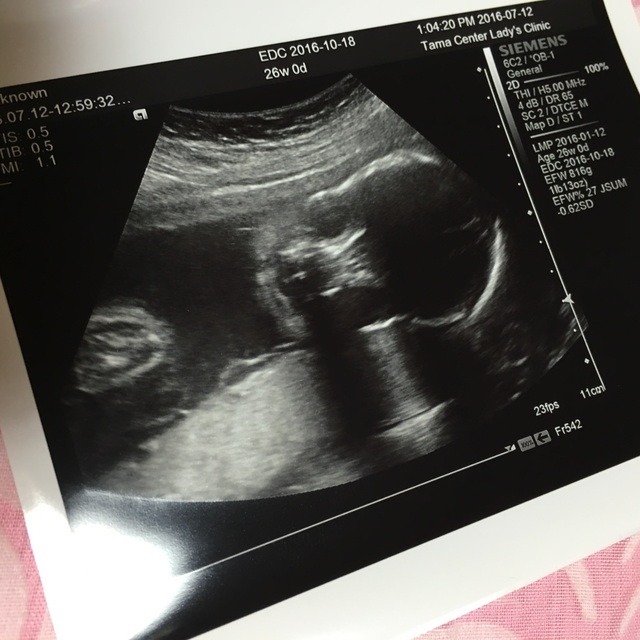

26週0日(26w0d・女の子)|あやんだ さん(25歳)

エコー写真撮影時のエピソード:

これが初めて顔が正面から撮れたときのエコーでした。

それまでは横顔だったり、手で見えなかったりしていたので、やっとハッキリ顔がわかる写真が撮れて、成長してるなー!っていうのが実感出来た時でした。

この写真が「コアラ」みたいだなーと思って、この日からコアラちゃんって呼んでました。 顔が見えると主人も愛着が湧いてきたようで 「早く子どものもの揃えないとね!!」と張り切り出したのもこの頃でした。

もう生後8ヶ月ですが、こんな頃もあったなーと懐かしいですね。